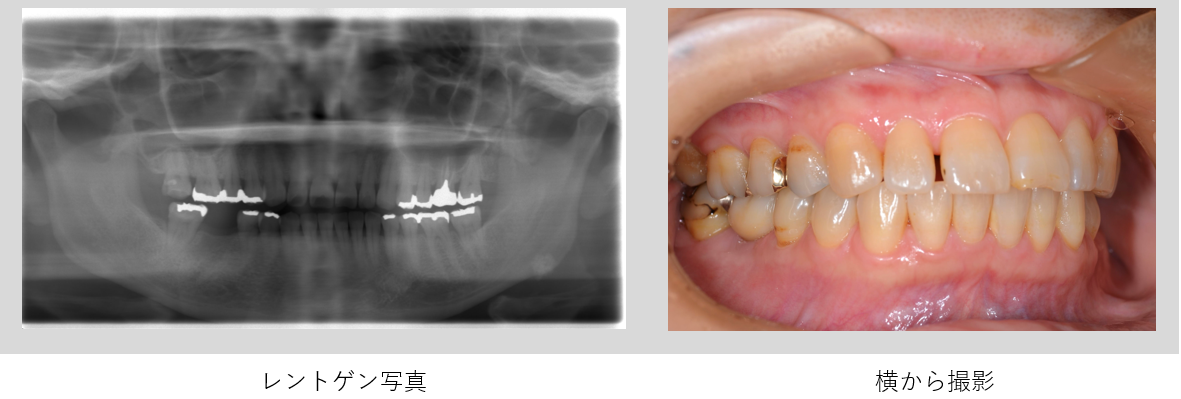

ケース2

| 年齢・性別 | 54歳・女性 |

| 主 訴 | 被せ物が合わないのでやりかえたい |

| 治療部位 | 右下6番 |

| 治療期間 | 6ヶ月 |

| 治療費 | インプラント審査診断:55,000円 インプラント体埋入:165,000円 上部構造(ジルコニアステインクラウン):165,000円 合計385,000円 (2023年7月現在) |

| 治療内容 | 右下5番6番 インプラント埋入、GBR、FGG、インプラントTEK、インプラント上部構造(ジルコニアステインクラウン)、サージカルガイド |

| 治療の リスク |

天然の歯と比較すると歯ぐきのトラブルが生じやすい 天然歯の歯ぐきには細菌の侵入を防ぐための線維のバリアが存在していますが、インプラントには線維のバリアが存在しません。 そのため、インプラント周りの歯ぐきや骨は細菌感染を起こしやすいと言えます。 しっかりとしたメンテナンスをしないとインプラント周囲炎になり、最悪の場合はインプラントを撤去する必要が生じます。 |

| 治療方針 | 初診時に右下6番は、歯の根が割れているので保存不可と診断しました。その後右下6番は抜歯を行いました。抜歯後しばらく欠損の状態でしたが、右上6番の挺出(※1)が認められた為、インプラント治療を行うことになりました。 骨造成は行わずに埋入手術を行いました。埋入手術から3ヶ月後に上部構造の型どりを行いました。そして手術から5ヶ月程で上部構造の装着をしました。 骨造成を行わないことで外科手術が最小限に抑えられ、治療期間を短く終えることができました。 ※1:挺出 かみ合う歯がなかったり、隣の歯がなかったりする事が原因で、歯が本来あるべき場所から突出してしまったり、移動してしまう事 |

| 特記事項 | 抜歯後しばらく時間が空いていたので、骨と歯ぐきが失われ、抜いた場所は歯ぐきが凹んだ状態になります。 本来であれば骨造成(GBR)を行い、失われた骨を再建した方が、歯ブラシがしやすい歯ぐきとなりセルフケアがしやすくなります。 |

| メンテナンス担当者所見 | 天然歯と比較して、インプラントの上部構造は根元の部分に汚れが溜まりやすい構造となっています。 また、今回骨造成を行わなかったので、通常よりも歯ぐきが凹んだ状態になり、汚れが溜まりやすくなっています。 そこでセルケアではルシェロ歯ブラシI20の使用を提案しました。インプラントと隣在歯の間は、歯間ブラシを使用してケアを行っています。 |